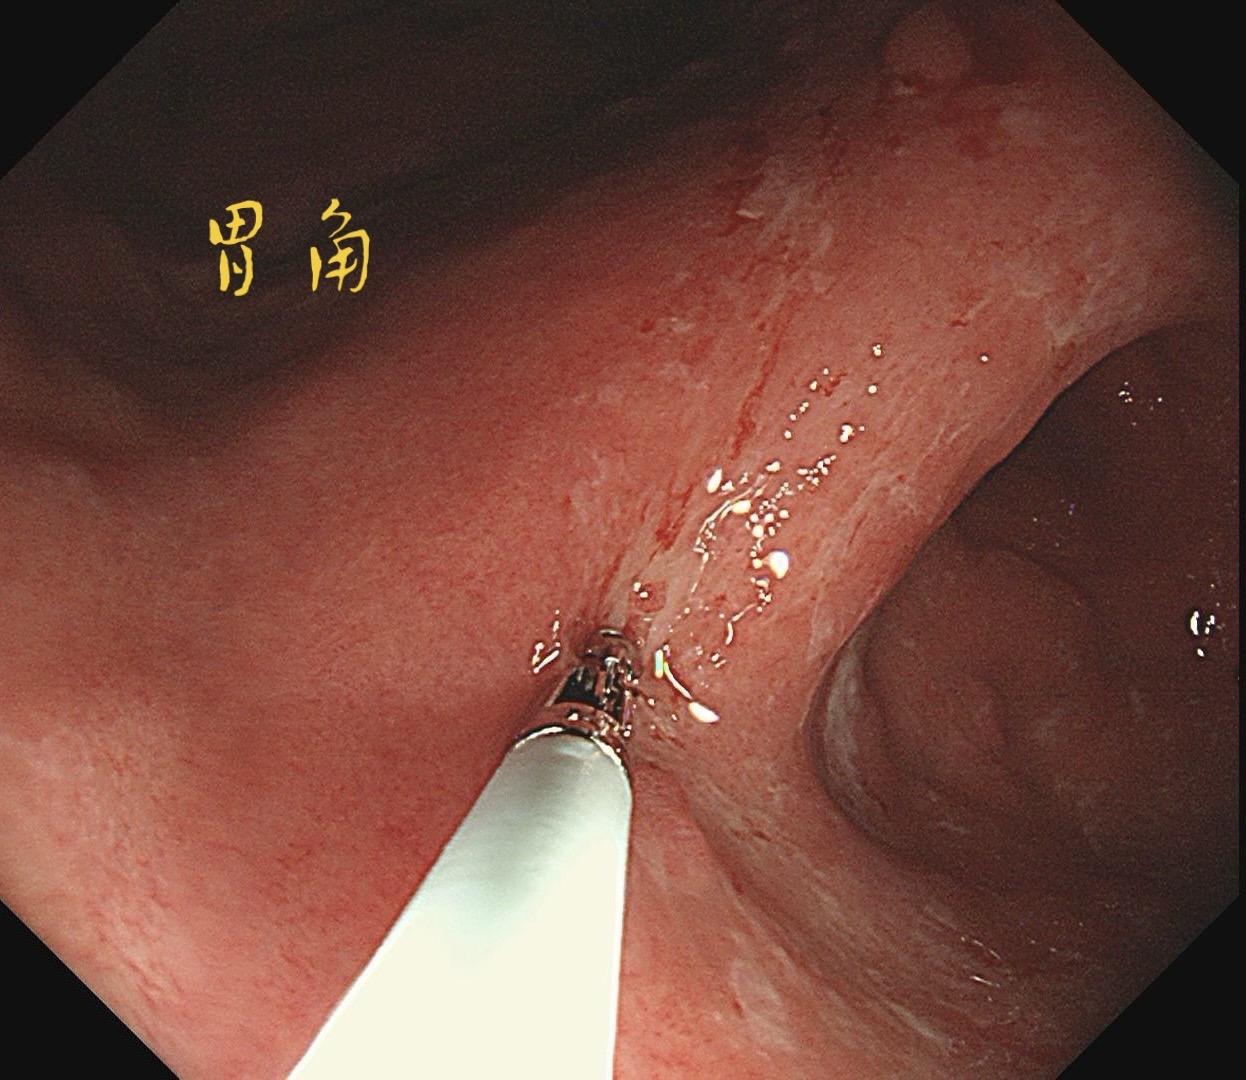

男,61岁,胃巨大褪色调病变。答案在最后一张图片,你猜对了吗? 患者因上腹部饱胀行胃镜检查,Hp阴性背景,胃窦至贲门下见一巨大褪色调病变,边界清晰,病变相对表浅,未见明显溃疡及隆起,胃壁较柔软,充气顺应性佳,予多点活检确诊,拟外科手术行全胃切除。做这么多年胃镜,还是第一次遇到这样的……